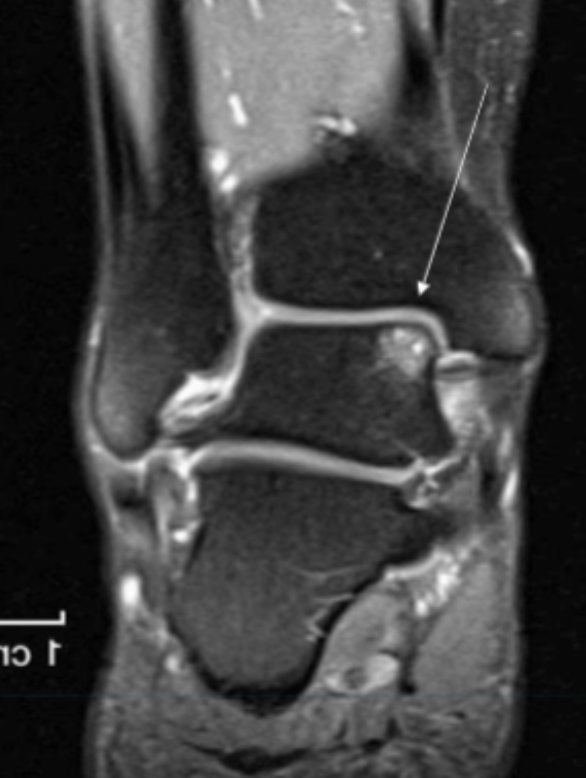

Describe the pathology indicated by the arrow (Cor T2 FS).

Osteochondral defect